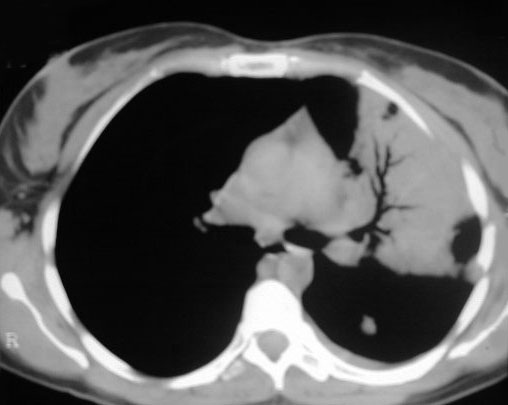

SIGNO DE LA DENSIFICACIÓN VERTEBRAL

Signo de condensación pulmonar en la radiografía lateral de tórax. En la radiografía lateral normal, la densidad de la columna torácica tiende a disminuir desde la parte superior hasta el diafragma; la alteración de ese patrón por la presencia de una densidad superpuesta a la columna (área marcada), indica la existencia de una consolidación pulmonar. Este signo adquiere especial valor cuando en la proyección posteroanterior la consolidación está oculta en el espacio retrocardíaco o en la base pulmonar.